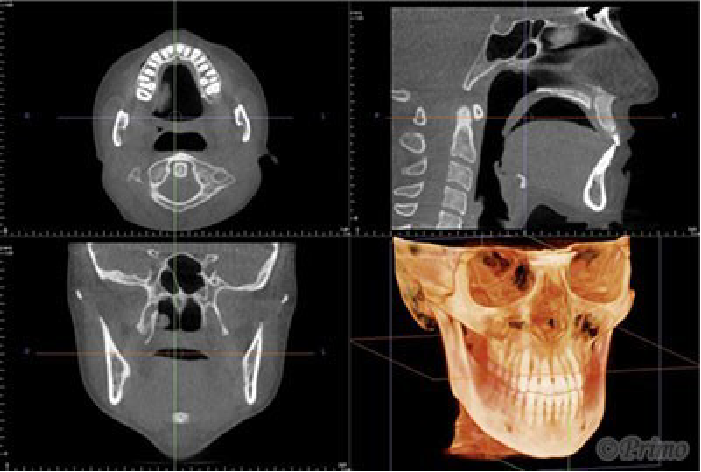

東京の美容外科クリニックではまだ数院しか導入されていないCT撮影装置を院内に備えております。顔面骨や鼻の形態を診断する際にたいへん威力を発揮致します。

当院での用途は顔面骨の大きさ、神経管からの距離の測定、骨切り後の状態の診断、鼻のプロテーゼの位置、大きさの測定、曲がりの診断や、鼻中隔湾曲症、斜鼻の診断、他院鼻中隔延長術後の変形などの診断にCTを頻繁に用いております。

一度の撮影で、診断からオーダーメイドプロテーゼの作成、骨実体モデルの作成が可能です。

当院手術後のフォローアップにもCT撮影はとても有用です。

CT撮影装置とは、円錐形のX線ビーム(コーンビーム)を照射しながら回転撮影を行う装置です。

通常のX線撮影では立体的な体を2次元の平面で撮影するため、詳細な情報を得られず診断が難しくなることがあります。一方CT撮影では、撮影した画像データから高画質な3D画像を作成し、得られた画像から患者様の頭部の骨の状態を、骨の内側の細部まで、3次元的に把握し診断することができます。顔面輪郭形成において、CT撮影は非常に有用になります。

広範囲な撮影領域

撮影領域は診断目的に応じて選択でき、口腔内に焦点を当てた直径8cm×高さ8cmの小範囲から、最大で直径23cm×高さ17cmの範囲をカバーします。頭部のほぼ全ての画像データを取得することができ、顎顔面領域の矯正治療において非常に有用になります。